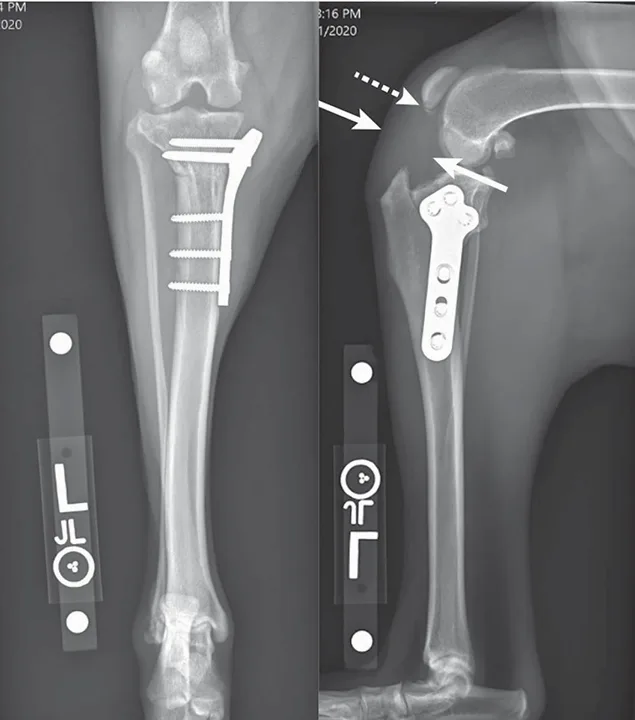

Figure 4

Radiographs from a 7-year-old spayed golden retriever presented with recurrent lameness 3 months after TPLO. A moderate weight-bearing lameness and pain on palpation of the cranial stifle/patellar tendon was identified on examination of the operated limb. Radiographs revealed thickening of the patellar tendon (solid arrows) and an apical patellar fracture (dashed arrow). Lameness resolved with rest, NSAID therapy, and shockwave therapy.

Intra-Articular Screw Placement

Intra-articular screw placement likely leads to persistent pain and hastened osteoarthritis development if not addressed immediately. The incidence of intra-articular screw placement during TPLO ranges from <0.1% to 7.1%.6,12,19,20 In one study comparing the use of locking and nonlocking TPLO plates, nonlocking TPLO plates were associated with an increased risk for intra-articular screw placement; this is likely because locking TPLO plates are typically precontoured with a screw trajectory designed to minimize the risk of intra-articular or intra-osteotomy screw placement.20 However, poor plate positioning, intraoperative plate contouring, or cross-threading can affect screw trajectory and result in intra-articular screw placement when using locking plates (Figure 5).20 Postoperative radiographs must be scrutinized for intra-articular screws, and offending screws must be immediately redirected or shortened to prevent the long-term effects of this complication.

Featured Image

Figure 5

Radiographs from a 5-year-old neutered male Bernese mountain dog with persistent lameness 2 months following TPLO. Radiographs revealed the proximal-most screw violating the joint space (arrow). This is best visualized on the third (oblique) view and was not identified on immediate postoperative radiographs. The locking plate is designed to reduce the risk of intra-articular screw placement, but this plate was contoured intraoperatively to accommodate for excessive medial buttress, which resulted in a screw trajectory directed toward the joint space.